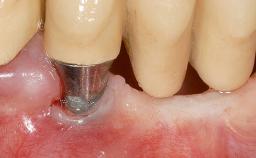

Early Implant Placement, Contour Augmentation, and Autologous Connective-Tissue Graft Using a Tunneling Technique to Replace an Upper Incisor with Generalized Gingival Recession

| # of Implants | 1 |

| Type of Implants | Reduced-Diameter|Two-Piece |

| Abutment Type | CAD/CAM |